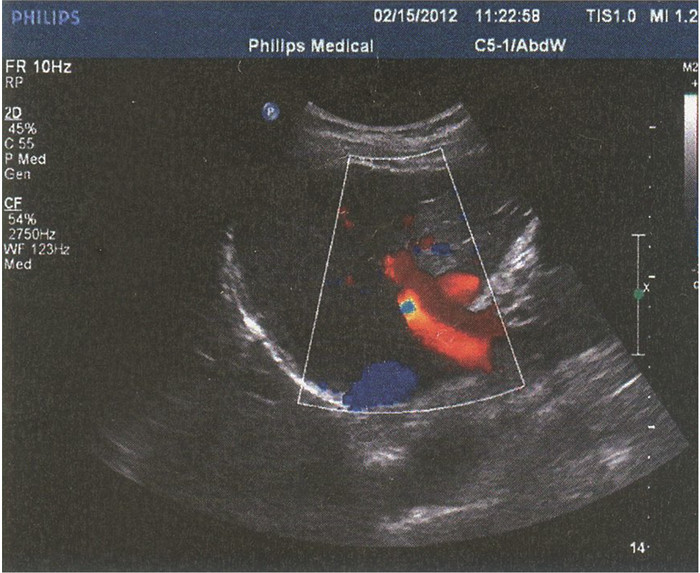

门静脉性胆道病1例报告

姜朋, 王树鹏, 刘亚辉

2022, 38(2): 430-432. DOI: 10.3969/j.issn.1001-5256.2022.02.034

摘要(715) HTML (239) PDF (2686KB)(52)

摘要: